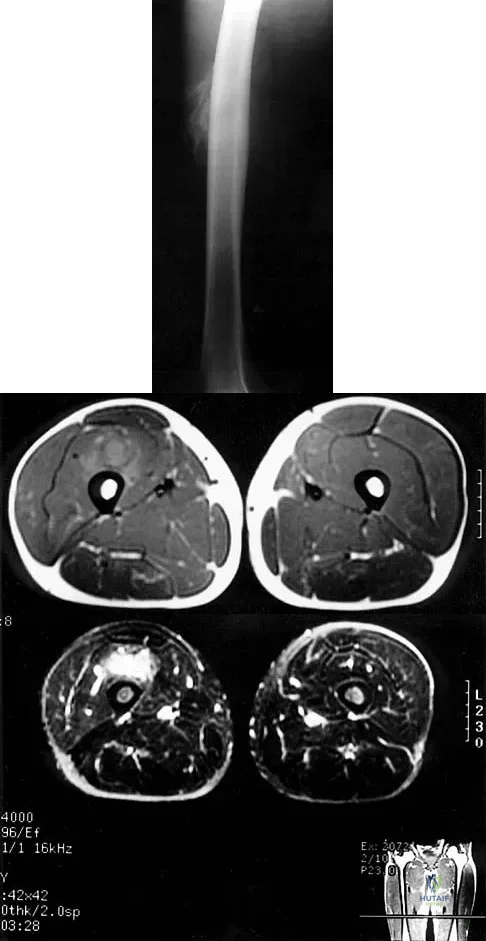

Question 96

Figures 8a through 8c show the lateral radiograph and T1- and T2-weighted MRI scans of a 14-year-old soccer player who reports aching thigh pain. The next most appropriate step in management should consist of

Explanation